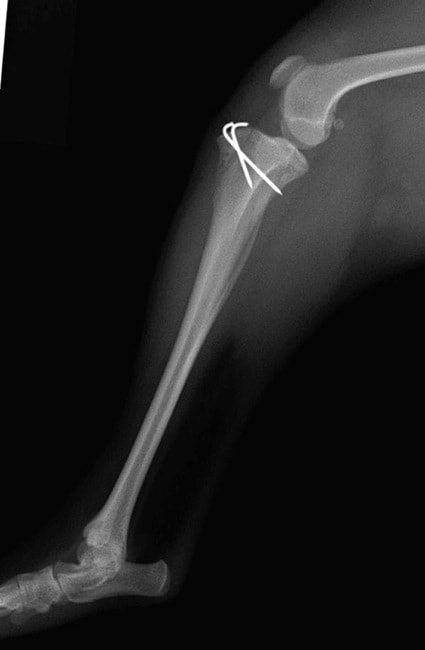

■ 症例22 ポメラニアン 1歳5か月 去勢雄

左後肢の挙上を主訴に来院した。整形学的検査、レントゲン検査より左右の膝蓋骨脱臼(左GradeⅡ〜Ⅲ、右Grade Ⅱ)を認めた。また、脛骨の前方引き出し試験の際に、引き出し兆候は認められないものの、疼痛が認められたため、前十字靭帯の損傷が疑われた。術中における、目視および関節内の操作によって、前十字靭帯の損傷や過伸展といった異常が認められなかったため、膝蓋骨脱臼の整復のみ実施した。手術手技は縫工筋及び内側広筋の解放、脛骨粗面の外側転位、滑車ブロック形造溝術、内外側関節包の縫縮を実施した。本症例は跛行もなく経過良好である。しかし、頸骨高平部の角度(TPA)が 右26.2°、左24.9°であり、解剖学的に前十字靭帯損傷のリスクが高いことから今後の経過に注意が必要である。